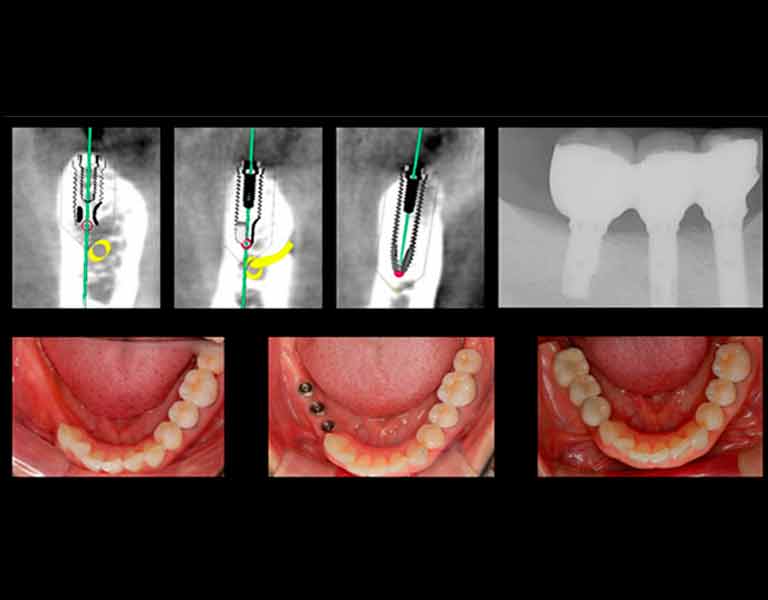

そして、インプラント治療のナビゲーションシステムと言えるシステムが「デジタルインプラント」です。

本書において、この「デジタルインプラント」とはどのようなものか?

そして今までのインプラント治療とどう違うのか?をお話していきたいと思います。